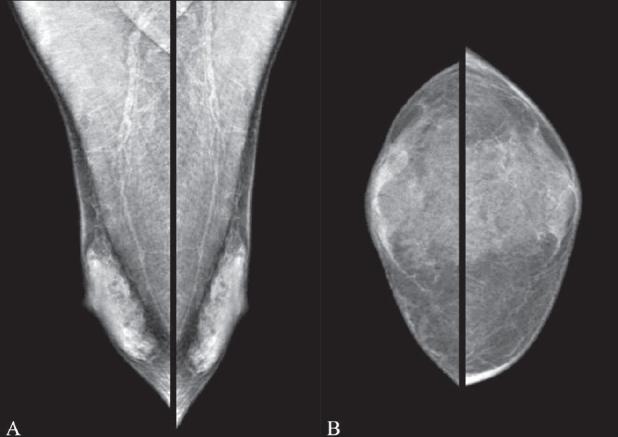

Pictorial essay: Mammography of the male breast.

Mammography is an imaging modality that is widely perceived to be of use only in women for the detection and diagnosis of breast pathologies. Here, we present a pictorial essay on the mammographic spectrum of male breast pathologies.

乳房X线摄影是一种成像方式,人们普遍认为它仅用于女性乳房疾病的检测和诊断。在此,我们展示一篇关于男性乳房疾病乳房X线摄影谱的图文文章。